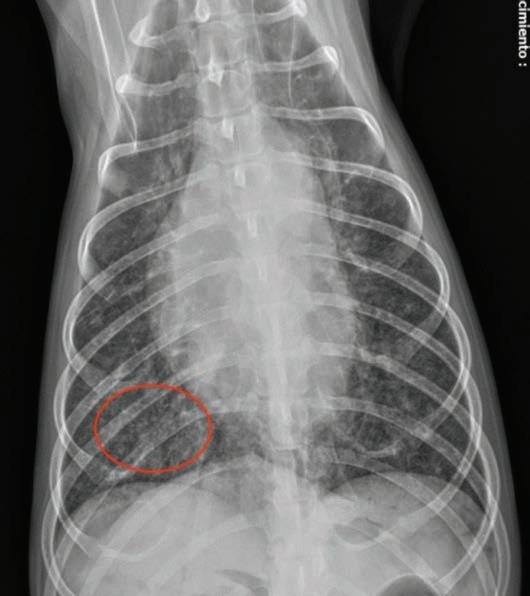

Se presentó en el Hospital Veterinario una perra esterilizada, mestiza de Rottweiler de 10 años de edad y 38 kg (Fig. 1), por la presencia de una masa de aspecto esférico de 1x1 cm en el aspecto lateral de la rodilla derecha. Como antecedentes clínicos, presentaba infección por Leishmania actualmente inactiva y sin tratamiento, cirugía correctora (TPLO) de rotura de ligamento cruzado craneal en la extremidad posterior derecha (EPD), realizada 294 días antes de la presentación actual, e incontinencia urinaria tratada con estriol.

Se realizó una citología de la masa en la que se observaron mastocitos de aparente bajo grado de malignidad según la escala de Kiupel1 (Fig. 2). Tras la evaluación preanestésica, en la que se incluyeron hemograma y bioquímica sanguínea, radiografías del tórax, ecografía abdominal y ecocardiografía, no se observaron alteraciones sistémicas relevantes, salvo una ligera leucopenia y neutropenia [leucocitos: 4,34 x 103/μl (ref.: 5,20-14,00 x 103/μl); neutrófilos: 2,35 x 103/μl (ref.: 3,10-11,00 x 103/ μl)]. La paciente se clasificó como ASA II.